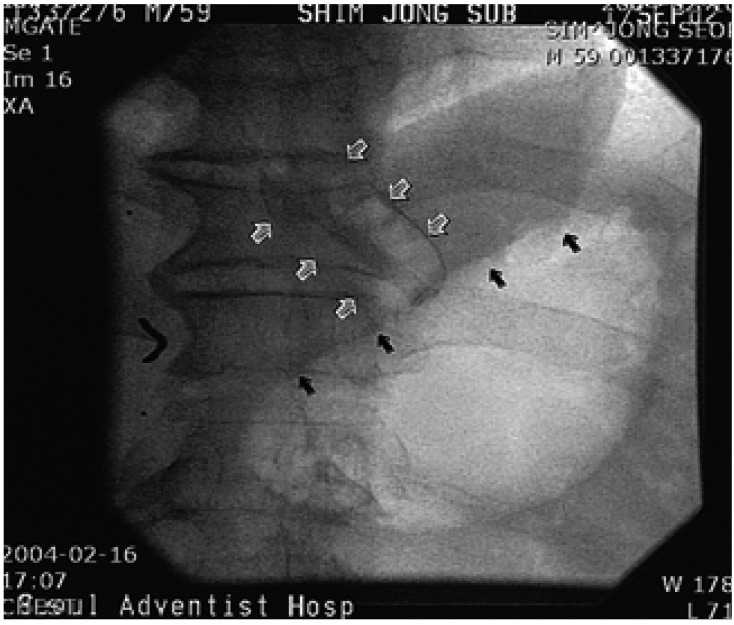

A 59-year-old man was admitted to hospital for the evaluation of syncope. The patient had been in good health except for when hypertension was detected 20 years earlier, and he had subsequently been treated for 3 years. Since he was about 30 years old, he had experienced many episodes of syncope when drinking a carbonated beverage (eg., a soda pop) and beer. About 4 years ago, syncope occurred while drinking cold water when he was taking a bath. Eating sticky foods such as a sweet potato, or even fast running caused syncope. The physical examination and routine laboratory results were normal except for a slightly increased serum creatinine level (132.6 µmol/L). Electrocardiography and chest X-ray findings were not specific. The left ventricular ejection ventricular hypertrophy was detected. A brain CT was normal. A carotid massage did not evoke any abnormal rhythms. Holter monitoring showed a sinus arrest with a maximum 7.2 seconds pause while drinking beer and a carbonated beverage (Figure 1A, 1B). An esophagogastroscopy, performed to search for an abnormality in the esophagus and stomach, showed only superficial gastritis at the fundus. Gastric distension by air could not induce syncope or an abnormal rhythm. An esophageal manometry showed no specific esophageal motility disorder except for transient low pressure in the lower portion of the esophagus. The patient was treated with a permanent pacemaker. After backing up the permanent pacemaker, esophageal balloon inflation by a Sengstaken-Blakemore tube with the pressure of 40 mmHg at the lower esophagus induced marked sinus bradycardia (Figure 2). However, no response was observed at the middle and upper esophagus.

A 59-year-old male was referred to hospital for the evaluation of about four episodes of syncope which he had experienced for 1 year. The first episode occurred with a loss of consciousness for 5 minutes following eating foods with feeling obstruction in the esophagus. No specific kinds or forms of foods had been associated with the symptom. He had experienced syncopal episodes usually right after eating, but sometimes while eating foods. The patient had been in good health except for having about ten episodes of an obstructive feeling while eating for 3 years. The result of an esophagogastroscopy conducted 1 year ago had been normal. Physical examination results showed no abnormality. The laboratory FT4: 26.445 pmol/L, TSH receptor antibody 30.5%). The blood count and liver function tests were normal. An electrocardiography showed sinus bradycardia (57 beats per minutes). A chest X-ray showed a compression fracture at the lower thoracic spine. A thyroid scan showed no demonstrable abnormal finding. The Holter monitoring test could not be done for refusal of patient and rarity of the symptoms. Inflation of the balloon in the lower esophagus and gastroesophageal junction that was at the 9th thoracic spine level resulted in junctional rhythm (32~36 beats per minutes) with lightheadedness (Figure 3, Figure 4). However, an atropine pretreatment blocked this response (Figure 3C). A syncopal episode was considered to occur with eating a bolus of food in a hurry; thus, he was treated by changing his eating habits for syncope and given propylthiouracil for Graves' disease.